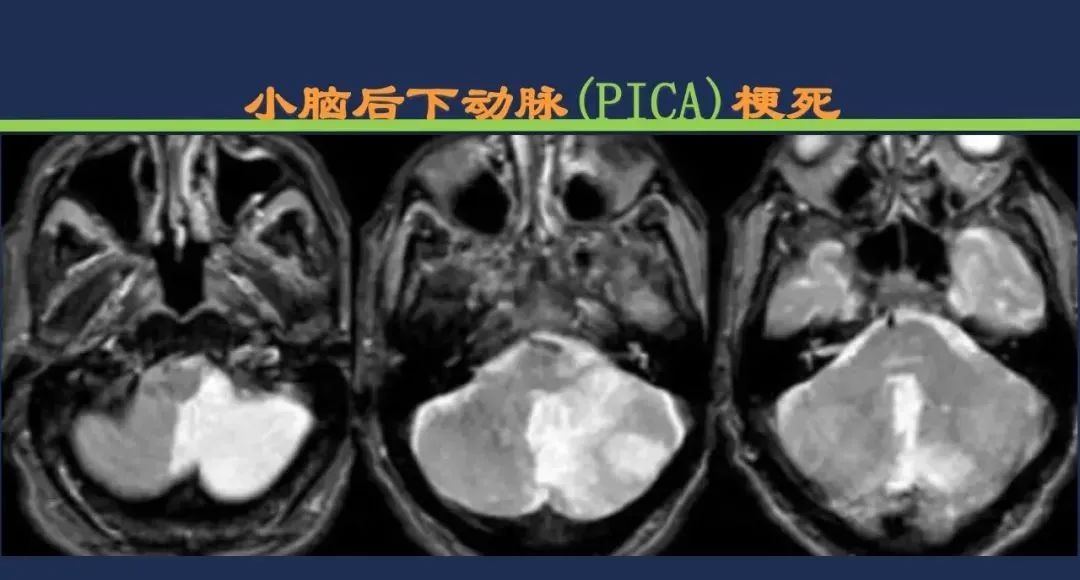

小脑后下动脉